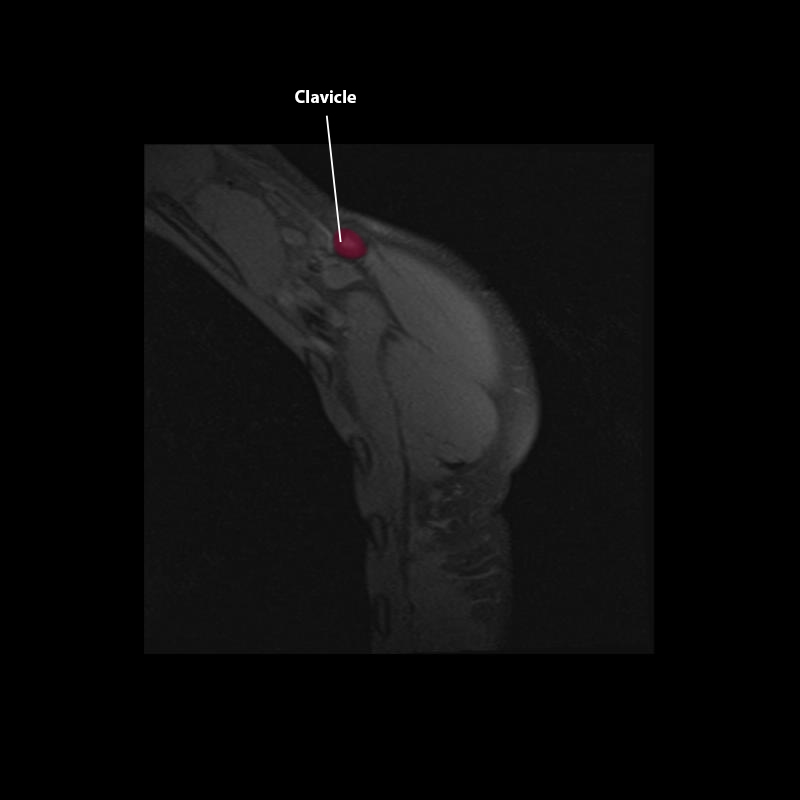

Shoulder MRI Anatomy